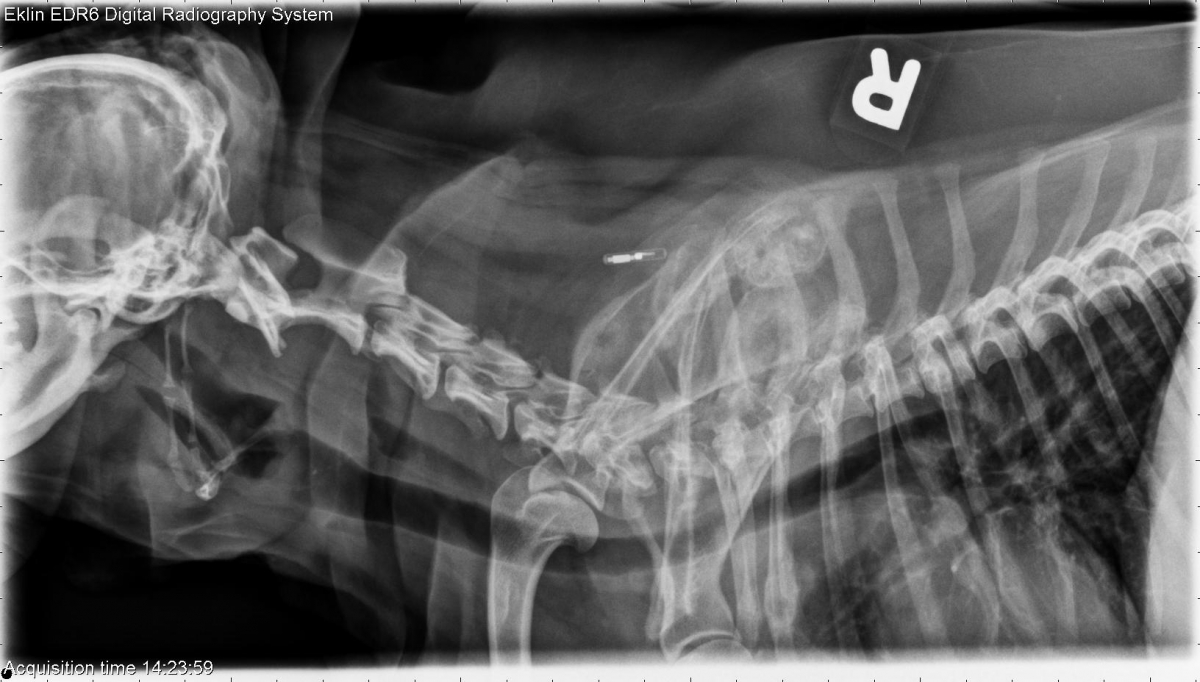

Today’s case is a 10 year old male neutered Yorkshire Terrier with hematuria and generalized pain. Can you find all the lesions?

R LAT Spine

Neck: There are multiple regions of lysis with surrounding sclerosis and smooth periosteal reaction in the scapulae, humeri, and ribs. The vertebral bodies appear normal.

Pelvis: There is smooth periosteal proliferation on the proximal lateral and distal medial right femur. The left femur and the tibia and fibula appear normal. No lesions are noted in the pelvis. There is amorphous soft tissue opacity in the left caudal abdomen.

Polyostotic aggressive bone lesions are most likely due to metastatic disease. Abdominal ultrasound could be performed to investigate for primary lesions and determine the cause of hematuria. Thoracic radiographs are recommended for metastasis check.

Prostatic carcinoma with multiple skeletal metastases.